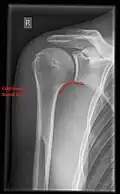

X-ray

Projectional radiography views of the shoulder include:

- AP-projection 40° posterior oblique after Grashey

The body has to be rotated about 30 to 45 degrees towards the shoulder to be imaged, and the standing or sitting patient lets the arm hang. This method reveals the joint gap and the vertical alignment towards the socket.[26]

- Transaxillary projection

The arm should be abducted 80 to 100 degrees. This method reveals:[26]

- The horizontal alignment of the humerus head in respect to the socket and the lateral clavicle in respect to the acromion

- Lesions of the anterior and posterior socket border, or of the tuberculum minus

- The eventual non-closure of the acromial apophysis

- The coraco-humeral interval

- Y-projection

The lateral contour of the shoulder should be positioned in front of the film in a way that the longitudinal axis of the scapula continues parallel to the path of the rays. This method reveals:[26]

- The horizontal centralization of the humerus head and socket

- The osseous margins of the coraco-acromial arch and hence the supraspinatus outlet canal

- The shape of the acromion

This projection has a low tolerance for errors and, accordingly, needs proper execution.[26] The Y-projection can be traced back to Wijnblath’s 1933 published cavitas-en-face projection.[27]